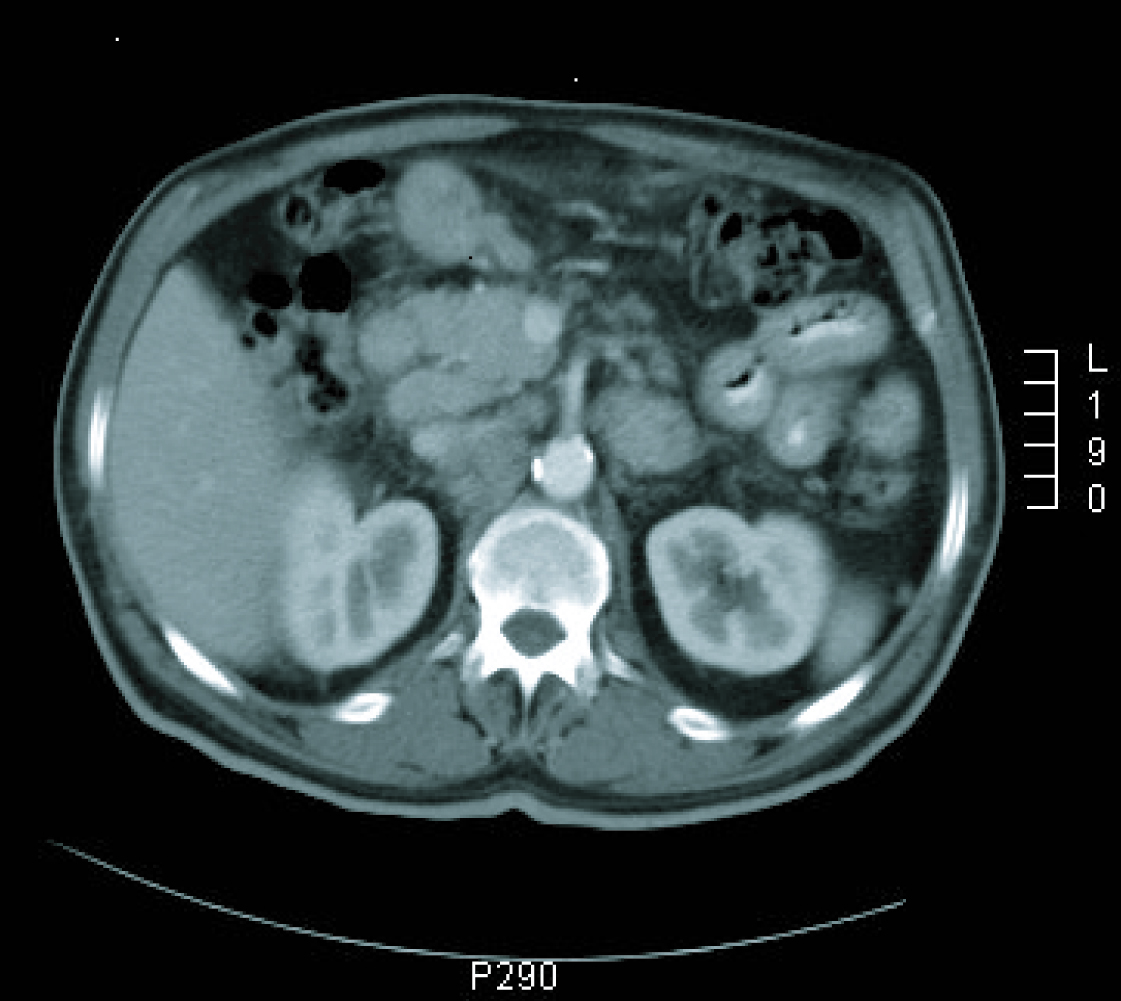

Gastroscopy revealed a 4 cm ulcer in the gastric antrum of uncertain malignancy and a 5 mm ulcer in the body of benign appearance. Anatomical pathology analysis confirmed a diagnosis of intestinal-type gastric adenocarcinoma. It was requested an extended study with CT imaging in order to analyse gastric wall and omental thickening and a number of lymphadenopathies in the gastric, abdominal and retroperitoneal regions (Fig. 1, 2). Analysis showed that tumour markers (CEA and CA 19.9 levels) were not elevated. Given a significant lymphatic component, it was decided to perform an ultrasound-guided fine-needle aspiration (FNA) of the adenopathy, which confirmed a metastatic origin of the adenocarcinoma. Evaluated as an oncology outpatient, the subject presented a maintained general state (with an ECOG 1 performance status), with examination showing a palpable mesogastric mass.

![]() Click for large image | Figure 1. CT imaging at diagnosis. |

![]() Click for large image | Figure 2. CT imaging at diagnosis. |